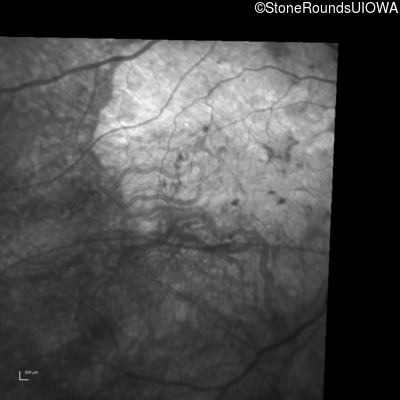

Infrared Fundus Photograph - Left - 20/200

Exemplar